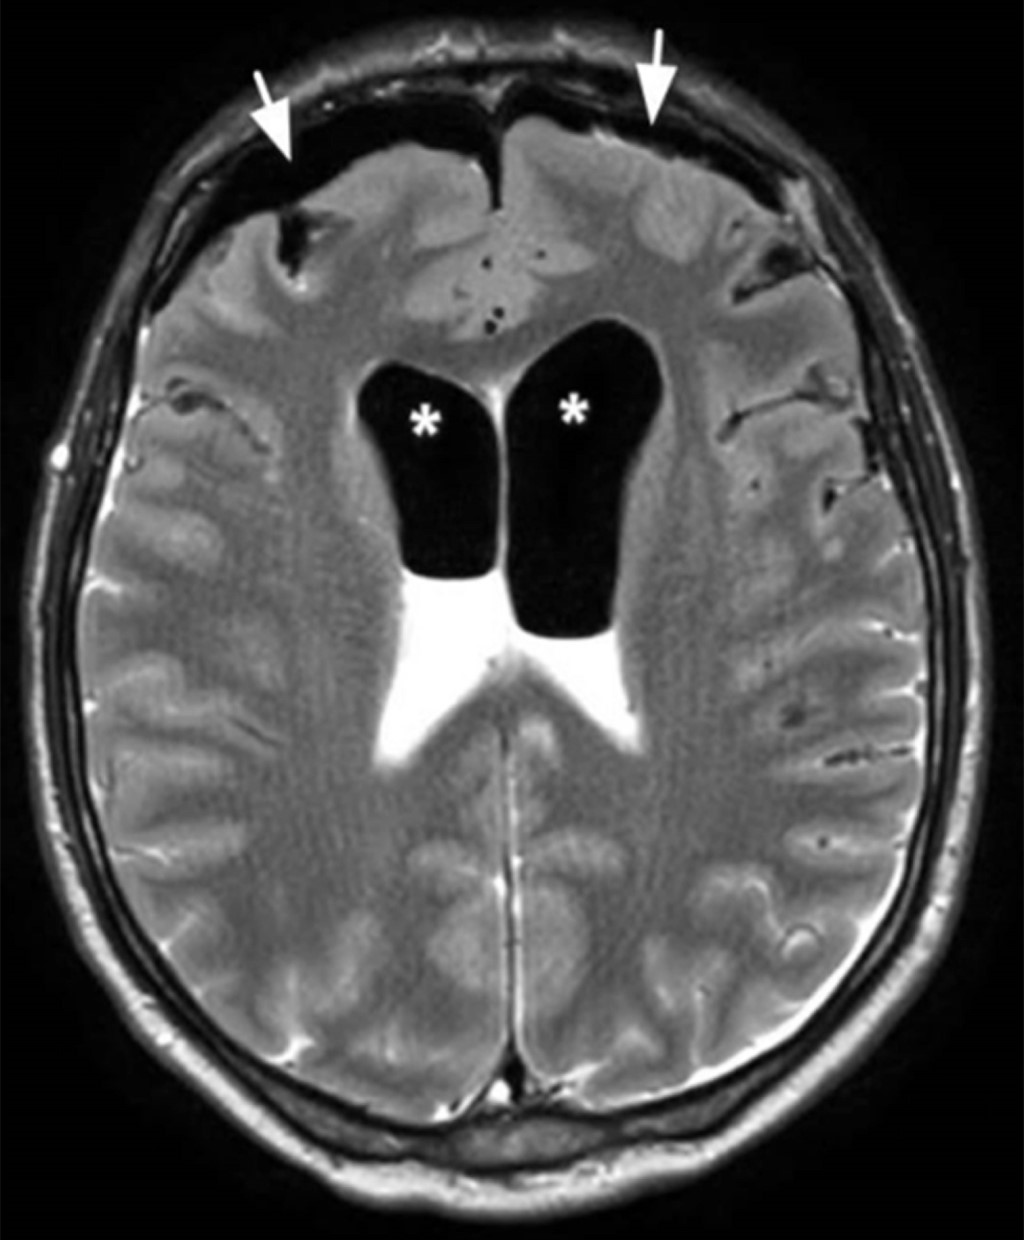

En el tercer día postoperatorio, el paciente presentó vómitos, cefalea, confusión mental y disminución del nivel de conciencia. La tomografía computarizada mostraba edema adyacente al lugar de inserción del tornillo frontal izquierdo, sin alteraciones en el parénquima encefálico o los ventrículos (Figura 3). El examen del líquido cefalorraquídeo mostraba signos sugestivos de proceso infeccioso (aumento de glucosa y proteínas). Se inició antibioticoterapia considerando la hipótesis diagnóstica de meningitis. El paciente mantuvo deterioro del nivel de conciencia. La exploración complementaria con resonancia magnética realizada después de once días mostró neumoencéfalo bilateral en la región frontal y en los ventrículos laterales (Figura 4). Diecisiete días después de la retirada del halo craneal, se realizó una tomografía computarizada que evidenció neumoencéfalo y neumoventrículo con signos de tensión y dilatación de los ventrículos laterales (Figura 5).